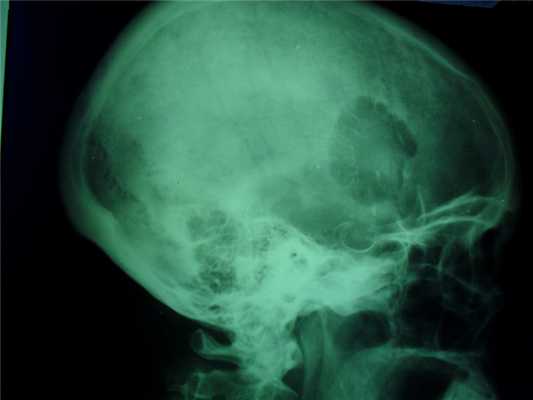

При локализации гемангиомы в плоских костях свода черепа происходит:

- вздутие кости и разрушение коркового слоя, надкостница приподнимается опухолью,

- характерен структурный рисунок - из центра опухоли к ее поверхности лучеобразно или веерообразно рассыпаются тонкие и более грубые костные балки.

В костях свода черепа ангиома представлена четко отграниченным участком перестройки костной структуры по мелкоячеистому типу. Чаще наблюдается незначительное вздутие кости, истончение и частичное разрушение наружной или внутренней костной пластинки и характерный лучеобразный структурный рисунок за счет различной толщины костных перекладин.